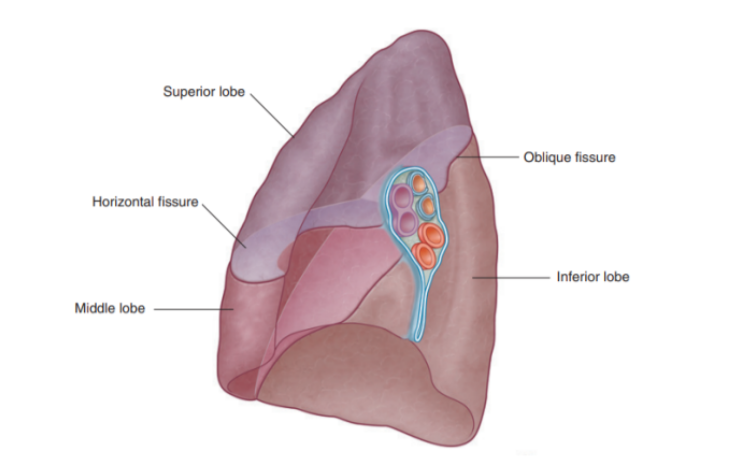

Fisssures of right lung

Has 2 fissures (formed by invaginations of the visceral pleura) —

Oblique fissure

Separates inferior lobe from superior & middle lobe

Horizontal fissure —

Separates superior lobe from middle lobe

Can be easily landmarked and correspond to specific ribs — important as they delimit zones of ascolatation

Lobes of right lung

Has 3 lobes — superior, middle, and inferior

Lobal attachment to surrounding mediastinal structures —

Superior lobe — in contact with the upper part of the anterolateral wall and the apex of this lobe projects into the root of the neck

Surface of the middle lobe — adjacent to lower anterior & lateral wall

Costal surface of inferior lobe — in contact with the posterior & inferior walls